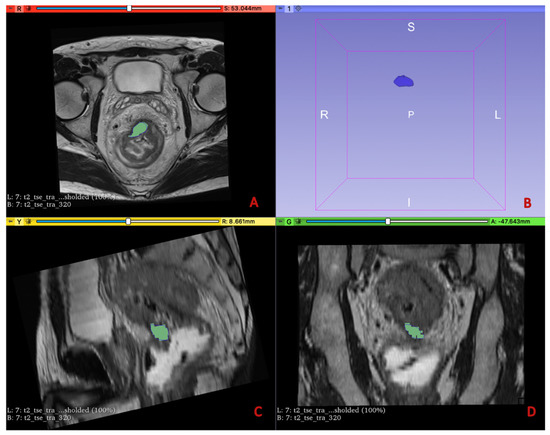

2.4. Imaging Analysis

2.5. Radiomic Workflow